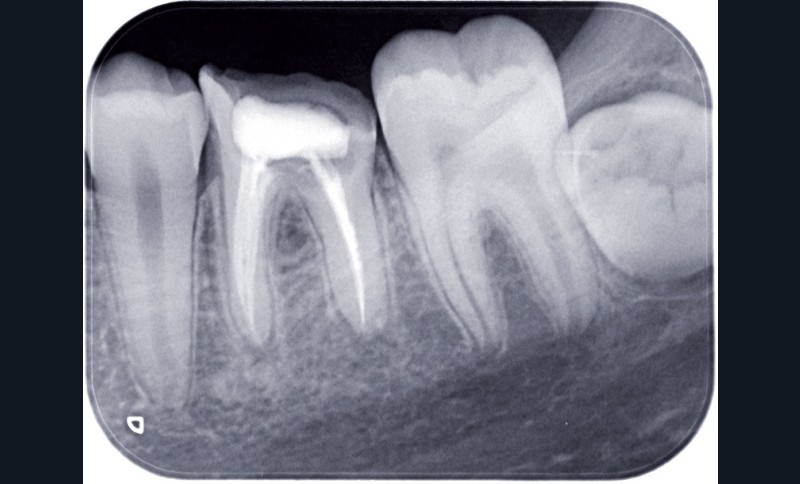

Examen radiographique

Le bilan rétro-alvéolaire révèle une atteinte du plancher radiculaire de 26 et 36 (fig. 10 et 11).